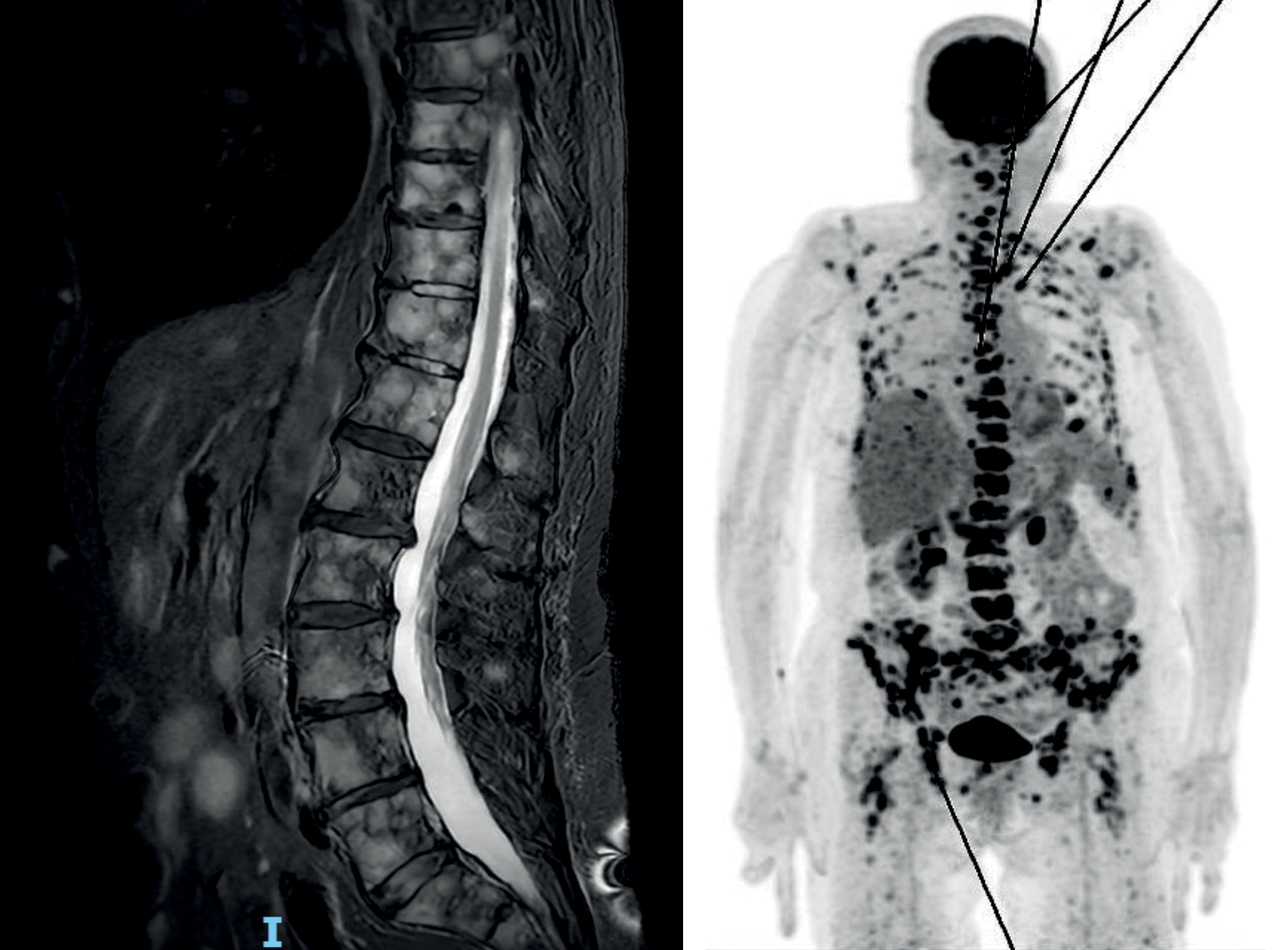

Une femme âgée de 87 ans est hospitalisée pour confusion et rachialgies. La calcémie est à 3,7 mmol/L. Une imagerie par résonance magnétique (IRM) rachidienne et une tomodensitométrie par émission de positons (TEP) sont réalisées.

L’IRM rachidienne montre des lésions osseuses de remplacement médullaire panrachidienne, associées à une atteinte sternale.

La TEP montre une adénopathie médiastino-hilaire sous-carénaire et de multiples lésions ostéolytiques intensément hypermétaboliques, d’allure secondaire.

Une biopsie ostéomédullaire met en évidence une localisation médullaire d’un carcinome indifférencié dont l’origine est probablement pulmonaire.

L’hypercalcémie est traitée par acide zolédronique.